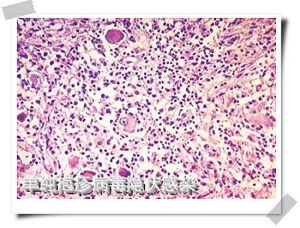

脫落細胞或皰疹基底刮片細胞學檢查,病變細胞增大有核內包涵體或呈多核巨細胞改變,雖陽性率可達60%~70%,但陽性改變非單純皰疹病變所特有。近年採用單克隆或多克隆抗體染色,特異性及敏感性均較高。

對新生兒單純皰疹病毒感染作出快速和特異性的診斷是基礎。感染可以通過人不同系列和非人類來源細胞的組織培養中分離到病毒而證實,病毒標本通常從皮膚水泡取得,口腔,眼睛和腦脊液也是產病毒的部位。在一些表現為腦病的新生兒,病毒僅能從大腦中發現。但是精確的測試(如單純皰疹病毒PCR檢測)只能在一些研究單位和特殊實驗室中進行,一般在24~48小時內可在組織培養中見到細胞病理反應,確診也可通過合適的高滴度抗血清作中和反應;用病損皮膚塗片作免疫螢光檢查,特別是使用單克隆抗體和電鏡檢查。如果無病毒學診斷設備,用病損基底部細胞,作帕氏塗片可顯示特徵性組織病理學依據(多核巨細胞和核內包涵體),但這一檢查的敏感性比培養差,並有假陽性出現。